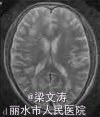

体温38.1℃,意识清楚,定向力、记忆力、计算力等高级皮质功能明显受损;脑神经阴性;四肢肌力V级,肌张力正常,腱反射(++),两侧对称;双侧巴氏征阴性,脑膜刺激征阴性。共济运动及感觉系统查体不能配合。全身浅表淋巴结未触及肿大,两肺未闻及干湿性I罗音,心律齐,腹平软,肝脾肋下未触及,双下肢无水肿。血常规示三系减低[白细胞计数3.6 X109/L(参考范围:4.0 X 109/L一10.0×109/L),红细胞计数2.15×1012/L(参考范围:4.00×10“/L一5.50×1012/L),血小板计数68×109/L(参考范围:100×109/L一300×109/L)],低蛋白血症[清蛋白28.5 g/L(参考范围:35.o一52.0g/L)];红细胞沉降率、肝肾功能及电解质均正常,维生素 B。:、叶酸正常,3次血培养均阴性;艾滋病抗体阴性;抗核抗体、肿瘤标志物、自身抗体及抗中性粒细胞胞质抗体(ANCA)阴性,免疫球蛋白M轻度降低[0.28 g/L(参考范围:0.46—3.04 g/L)];乳酸脱氢酶[1 120 U/L(参考范围:135—225 U/L)]和血13:微球蛋白[3.7 mg/L(参考范围:1.0—2.5 zng/L)]明显增高。腰椎穿刺脑脊液检查示:压力150 illln H20(参考范围:80—180柚H20,1 mm H20=0.0098 kPa),白细胞计数7×106/L[参考范围:(0—10)X100/L],蛋白2.80 g/L(参考范围:o.10—0.25 g/L),cl一107 rnmol/L(参考范围:120—130 n吡nol/L),糖3.5 mol/L(参考范围:2.5~4.5 mmol/L);细胞学正常;IgG指数0.099;JCV—DNA阳性;单疱病毒、柯萨奇病毒、埃可病毒、巨细胞病毒等抗体阴性;墨汁染色阴性,细菌加真菌培养阴性。2010—0l一19流式细胞术检查示co;/cD毒(85%)轻度增高,co;co;、coco;、cD五cD未基本正常,CDI;(2%)明显减低。2.3影像学检查2009—12—25腹部CT提示脾脏偏大, 2010-01—12复查腹部CT提示脾脏肿大、两侧肾上腺区团块影。2009—12—29颅脑MtlI示两侧半卵圆中心、侧脑室旁多发病变009—12—24骨髓穿刺检查示有核细胞增生活跃,红系/粒系(G/E)=0.87:1;中性粒细胞增生(占40.4%),以中性中间阶段粒细胞为主;红细胞增生(占 46.4%),以中晚幼红细胞为主;淋巴细胞比例下降;血小板计数较少,吞噬细胞增多,未见明显异常细胞

患者2009—12—27入住感染科,予头孢哌酮针及阿奇霉素针抗感染等治疗,病情无明显好转。2009—12—29行颅脑MPd检查示脑内多发脱髓鞘样病灶,于2010—01—06转入神经内科并行相关检查。根据该患者的临床和影像学特征,结合脑脊液中JCV的DNA序列检测以及骨髓穿刺病理活检结果,诊断为弥漫大B细胞淋巴瘤并发PML可能。虽经退热、补液,纠正贫血、低蛋白血症等积极治疗,但患者病情仍迅速进展,于2010—01—28凌晨出现呼吸、心搏停止,予气管插管、心肺复苏等积极抢救治疗后呼吸、心搏恢复。患者自动出院1 d后死亡,家属拒绝尸检

本例患者表现为视觉障碍、认知功能减退和精神行为异常等典型的PML症状,颅脑MRI检查符合典型的PML影像学表现;脑脊液中检测到JCV的DNA序列,病理活检证实弥漫大B细胞淋巴瘤侵犯骨髓,并且缺少其他感染或肿瘤的依据。因此,本例患者诊断为弥漫大B细胞淋巴瘤并发PML。PML患者通常处于免疫抑制状态,在此基础上需要与其他颅内多发病灶鉴别,如中枢神经系统血管炎、原发性中枢神经系统淋巴瘤以及脑弓形体病等。本例患者病史和实验室检查以及颅脑MRI表现均不支持以上疾病的诊断。目前,针对PML尚无特异的治疗措施,PML患者的预后极差,临床需引起足够的重视。当存在免疫缺陷或免疫抑制的患者出现典型的视觉障碍、认知功能改变、肌无力等症状时,应考虑本病的可能。本例患者虽经积极对症治疗,但患者病情仍迅速进展、恶化。因此,在病程早期行颅脑MRI检查以及腰椎穿刺脑脊液检测JCV的DNA序列,均有助于本病的诊断,必要时可行脑组织活检。明确诊断后应立即开始免疫重建治疗,抑制脱髓鞘的继续进展;同时避免医源性PML也非常重要。